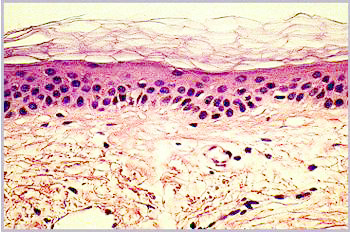

Aged skin can be recognized immediately by the presence of wrinkles, flaccidity and actinic keratosis. A histological section reveals some of the causes of these symptoms of ageing (Fig. 1 a and b).

Fig. 1a: Microscopic sections through the skin of a 21-year-old |

Fig. 1b: Microscopic sections through the skin of a 66-year-old |

Fig. 1

a and b

Microscopic sections through the skin of a 21-year-old and a 66-year-old

In young skin, the

lower part of the skin, the dermis, has a very regular structure. This

regularity is no longer so clear-cut in older skin. The dermis contains

irregular structures and flaws and appears less compact. The next highest

layer, the epidermis, is somewhat thinner in older skin than in younger.

More noticeable than this slight change in the thickness of the epidermis,

however, is the disappearance of the curvature of the epidermal-dermal

interface. In older skin this interface is flat, so that the cohesion

between dermis and epidermis is weaker. Finally, in the upper layer, the

stratum corneum, scarcely any differences can be observed under the microscope.

The main changes are therefore in the deeper layers of the skin, especially